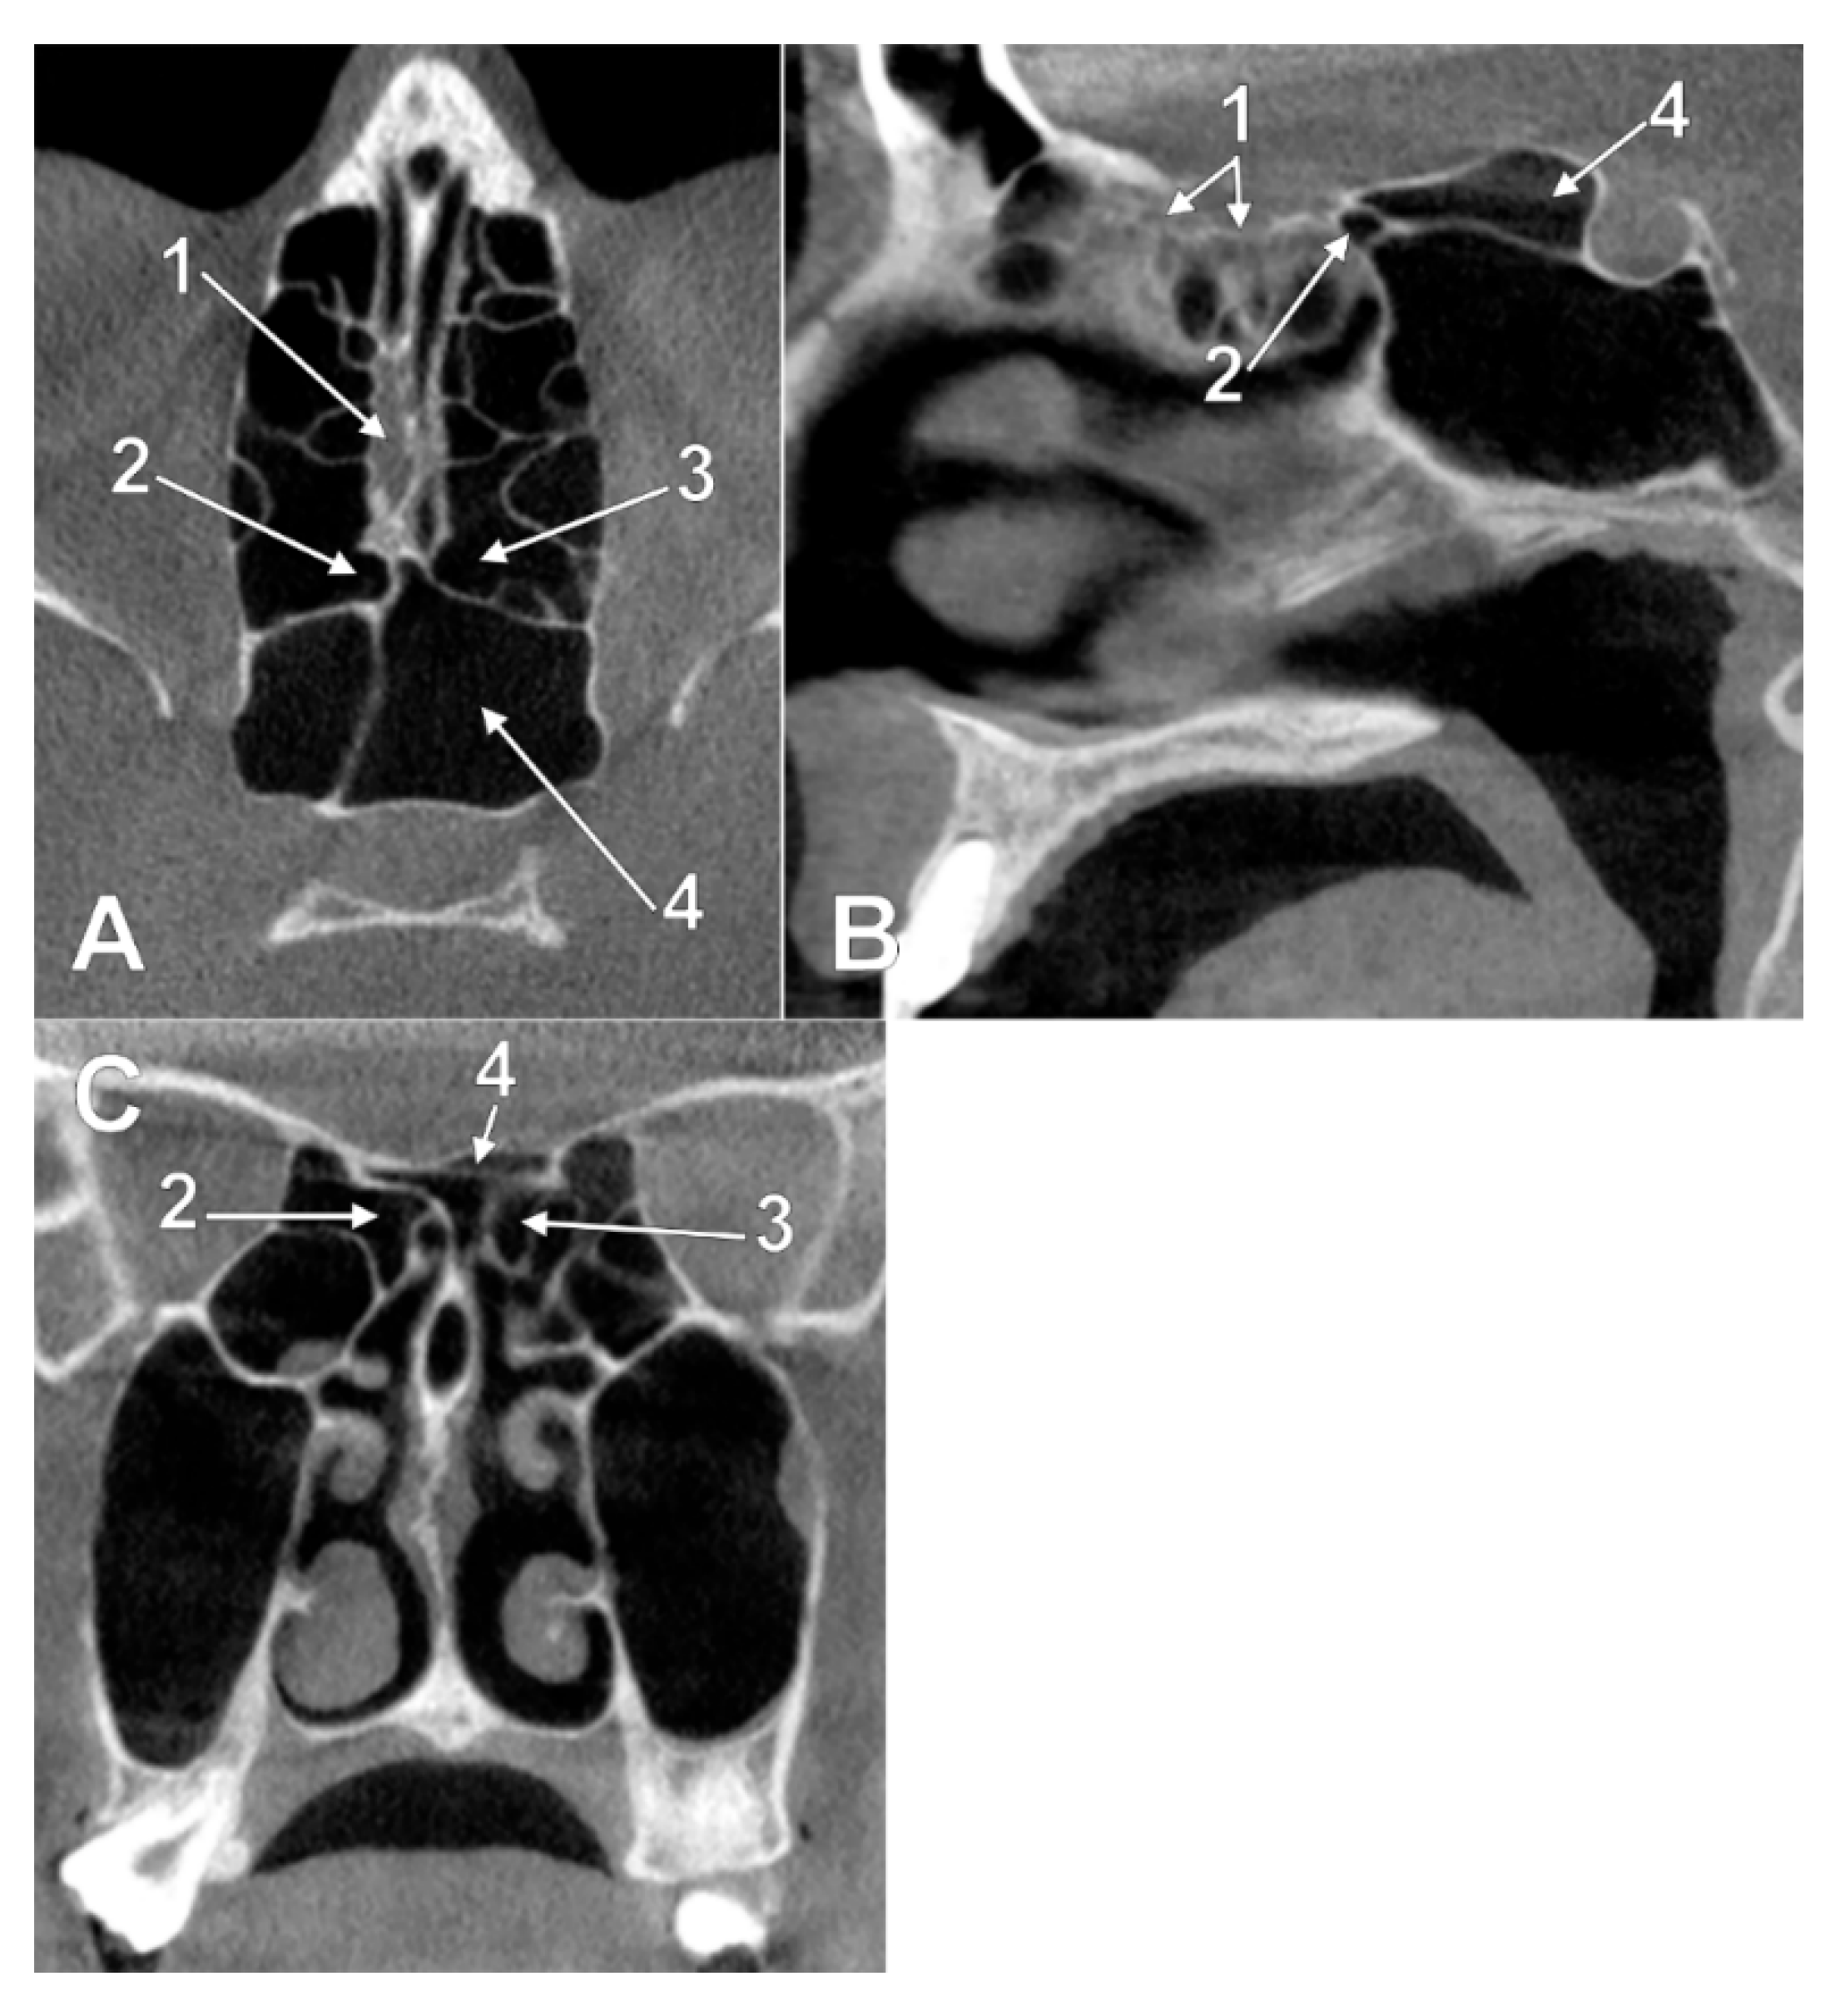

3.3. Sphenoethmoidal (Onodi Cell) Origin of Nasal Roof Pneumatizations